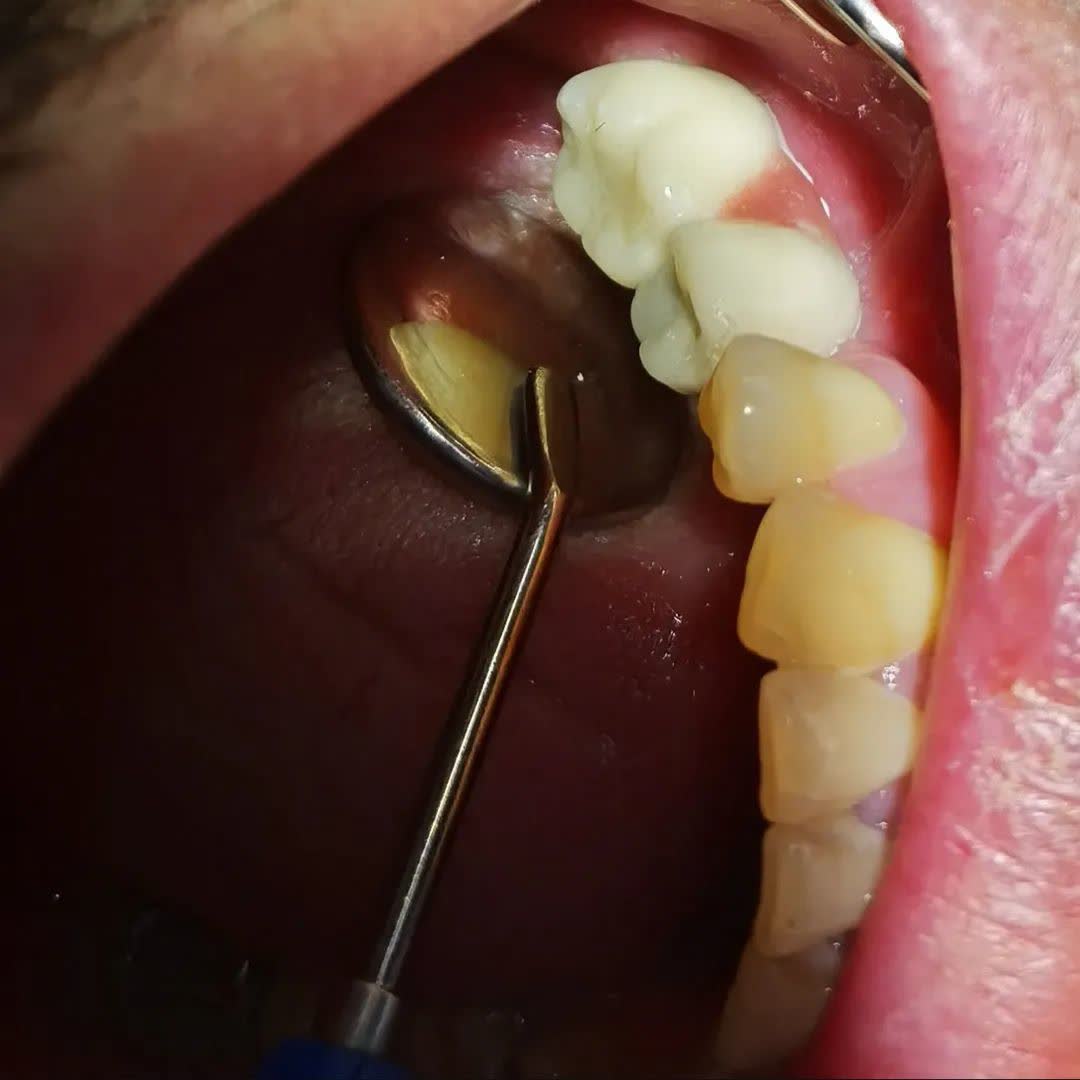

دکتر ناهید علیان نجف آبادی دارای دکترای حرفه‌ای دندانپزشکی است که در شهر نجف آباد فعالیت می‌کند. ایشان در حوزه درمان بیماری‌ها و مشکلات دهان و دندان تخصص داشته و از پزشکان برجسته در زمینه ایمپلنت و خدمات زیبایی دندان به شمار می‌روند.

• ایمپلنت دندان

• کامپوزیت ونیر و لمینت سرامیکی

• ترمیم دندان با روش بایومیمتیک

• ارائه خدمات دندانپزشکی زیبایی مانند لمینت و کامپوزیت